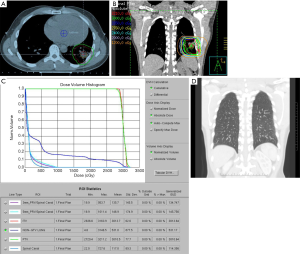

As gastric MALT lymphoma is often a multifocal disease, the radiation target volume should include the entire stomach, even in cases where the disease may appear to be confined to one region of the stomach. Lymph nodes are only included if they are suspected to be involved with the disease. In older RT series, patients were treated with extensive RT fields to the entire abdomen (5,40,41). Long term outcomes reported by Wirth et al. on behalf of the International Extranodal Lymphoma Study Group (IELSG) revealed that radiation field size and RT dose was not associated with increased treatment failure among 102 gastric MALT lymphoma patients in which 41 received RT to the whole abdomen and 61 were treated to the stomach and involved nodes (5). The German Study Group on Gastrointestinal Lymphoma performed stage adaptive RT field reductions over the course of 3 prospective trials for gastric MALT lymphoma patients without loss of local control but with lesser frequency of treatment related toxicities (42). Current recommendations from ILROG suggest that the CTV should encompass the stomach from the gastroesophageal junction to beyond the duodenal bulb as well as any pathologically involved nodes (15). Modern technology should be used to reduce doses to neighboring normal structures, including the heart, kidneys and spleen (Figure 1). As the stomach is subject to significant motion due to peristalsis, respiratory motion and variations in stomach filling, techniques and procedures directed at accounting for organ motion are essential. Patients should have NPO status at least 6 hours prior to therapy, four dimensional (4D) CT simulation or DIBH techniques should be used for treatment and PTV margins should be adjusted according to the image guidance technique utilized (Figure 1). With DIBH and daily CT image guidance, 1.0–1.5 cm margins are often used (43). With free breathing treatment and 2D imaging alignment to bony anatomy however, margins of 2.2 cm or greater have been shown to be necessary to achieve adequate PTV coverage (44). DIBH technique has been shown to be a promising strategy to reduce unintended radiation to the heart when treating gastric MALT lymphoma patients (45,46).

For patients presenting with stage IE or stage IIE disease, RT is recommended if the volume of lung exposed to radiation is not excessively large. Pre-RT assessment of pulmonary and cardiac function is important, and should include clinical evaluation, spirometry and diffusion capacity, and cardiac ejection fraction. The target volume encompasses the gross disease with a margin taking account of organ motion due to the respiratory cycle (Figure 6A). Established methods of motion management (e.g., DIBH) should be used whenever feasible. A RT dose of 24–30 Gy given in 1.5–2.0 Gy fractions over 2 to 3 weeks is prescribed (Figure 6B, C and D). As the lung tissue has limited tolerance to radiation (79,80), large target volumes result in a high risk of radiation pneumonitis and later pulmonary fibrosis with functional impairment. Therefore, if the tumor is bulky, or has significant pleural extension or malignant effusion, or if multiple lung nodules are present, conventional RT fractionation should not be used. Low dose RT with 2×2 Gy regimen can be very effective for local control (11). Otherwise, for more extensive disease chemotherapy is recommended. Lung tissue exposed to a dose of 30 Gy given in 2 Gy fractions or less have an approximately 40–50% chance of manifesting visible changes of pneumonitis on a CT scan (80). Factors that affect this risk include the volume of lung tissue irradiated, and the dose/fraction (81). The presence of RT changes in the lung can make response assessment difficult if residual treatment related abnormalities persist. For patients with small MALT lymphomas treated with complete surgical excision confirmed pathologically, RT may be unnecessary. If resection margins are positive, postoperative RT can be considered.